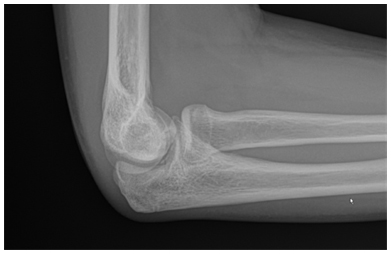

- Radiographs are used to detect the size, location and severity as well as skeletal age of the patient.

- Contralateral X-rays can help determine patients age as the affected side will have premature closure of the capitellum and radial head physes with delayed closure of the medial epicondyle and olecranon physes secondary to valgus stress overload

X-rays demonstrate a large lateral lesion within the capitellum consistent with an OCD lesion. The articular surface appears irregular

- Various classification schemes help determine severity. This includes:

- Grade I: Localized Flattening of articular cartilage

- Grade II: Nondisplaced fragmentation of the cartilage

- Grade III: Displaced or detached fragments/sclerosis or loose bodies

***Location of lesion on capitellum is important because lateral lesions tend to have inferior outcomes than central lesions

*** Throwing athletes tend to have more anterior lesions compared to gymnasts

- “Stable” lesions have been defined as those with open capitellar physis, localized flattening and radiolucency of subchondral bone with near normal elbow range of motion. Grade I is considered stable and Grade III is unstable. Grade II can be stable or unstable